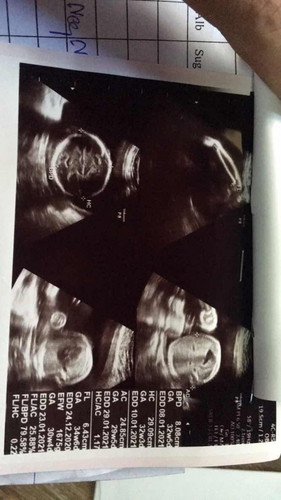

เราเพิ่งมารู้ว่าลูกเรามีโครโมโซมที่ผิดปกติตอน8เดือนกว่าใกล้คลอดแล้วค่ะ ที่แย่ที่สุดคือ น้องเป็นโครโมโซมคู่ที่18เกินมา1คู่ หมอบอกน้องคลอดมา ก็ไม่มีทางรักษาให้หายได้ อาจจะอยู่กับแม่ได้ไม่ถึงชั่วโมง ใครเคยมีประสบการณ์ ช่วยแชร์ประสบการณ์หน่อยค่ะว่าน้องคลอดมาจะเป็นยังไงบ้าง